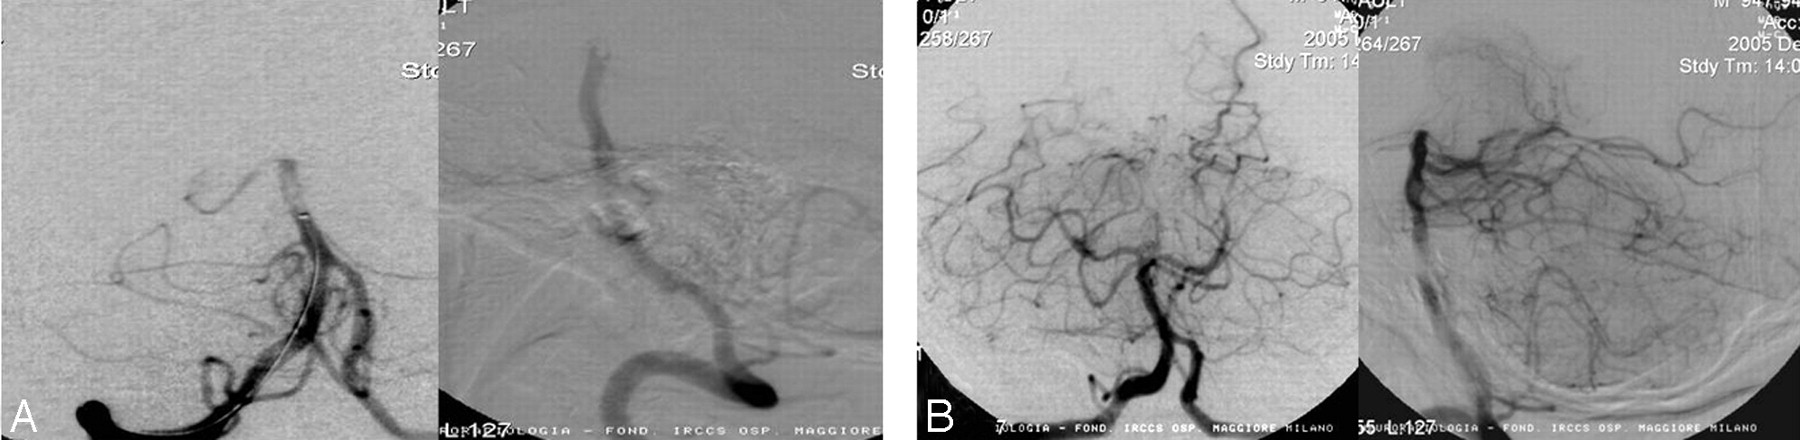

The primary end point for this study was incidence of revascularization of the target vessel as defined by achieving TIMI 2 or 3 flow after use of the PS (Fig 2).7 Each investigator made an initial assessment of TIMI flow in the target vessel preprocedure and postprocedure. Preprocedure and postprocedure angiograms were sent to an independent core laboratory to make a final determination on TIMI flow. Data based on core laboratory assessments were used for final analysis.

Angiographic illustration of a target vessel before (A) and after (B) treatment by the PS. This patient was a 66-year-old man who presented 3 hours from symptom onset with an NIHSS score of 24, which improved to 8 at 24 hours after revascularization by the PS. He continued to recover with a 30-day NIHSS score of 2 and an mRS of 1.